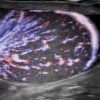

Viêm tinh hoàn - mào tinh

Viêm tinh hoàn – mào tinh

» Thông tin: Nam giới – 34 tuổi.

» Lâm sàng: Sưng đau vùng bìu.

# Tăng kích thước và tín hiệu mạch trên doppler tinh hoàn và mào tinh hoàn.